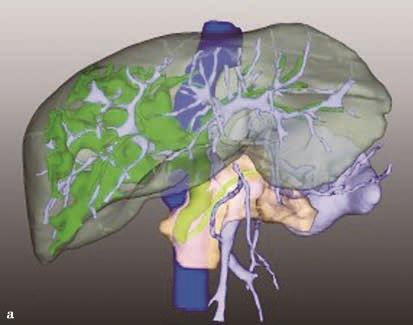

图2-5-1 采用不同栓塞材料实施PVE

A、a.弹簧微钢圈栓塞门静脉右支;

B、b.氰基丙烯酸正丁酯栓塞门静脉右支和Ⅳ段支;

C、c.微钢圈联合氰基丙烯酸正丁酯栓塞门静脉右支。

A.PVE术前CT;a.PVE术前三维可视化重建;

B.门静脉右支行弹簧微钢圈联合NCBA栓塞,术后2周复查CT见弹簧微钢圈移位至肝左外叶门静脉末梢支,肝左内叶见NCBA分布;b.PVE术后三维可视化重建,NCBA自门静脉右支移位至门静脉左内叶分支。